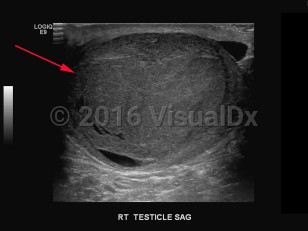

Testicular cancer

A malignant tumor of the testis (one or both), most often of germ cell origin (95%), which may be diagnosed as primary or metastatic cancer. Common presentation includes painless swelling, palpable mass or enlargement in the testis, orchidalgia, fatigue, and infertility. Other symptoms may be flank pain and dull or heavy abdominal sensation. Patients with metastatic disease, depending on the location of the metastasis, may present with gastrointestinal (GI) symptoms (nausea, vomiting, GI hemorrhage, anorexia), edema of extremities, bone pain, back pain, central nervous system abnormalities, cough, dyspnea, or neck mass. Patients with cryptorchidism have greater risk for testicular cancer.

Nonseminomatous tumors most commonly occur in patients aged 15-35, while seminomatous tumors target men a decade older. Germ cell malignancies of the testis are typically associated with a specific cytogenic irregularity (il2p). Non-germ cell tumors may arise in Leydig or Sertoli cells, or lymphomas, with non-Hodgkin lymphoma more common in men over age 60.